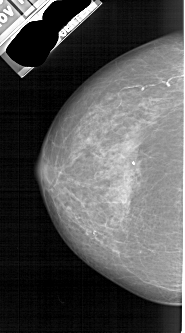

A_1889_1.RIGHT_CC

LEFT_CC LINES 4651 PIXELS_PER_LINE 2581 BITS_PER_PIXEL 12 RESOLUTION 43.5 NON_OVERLAY